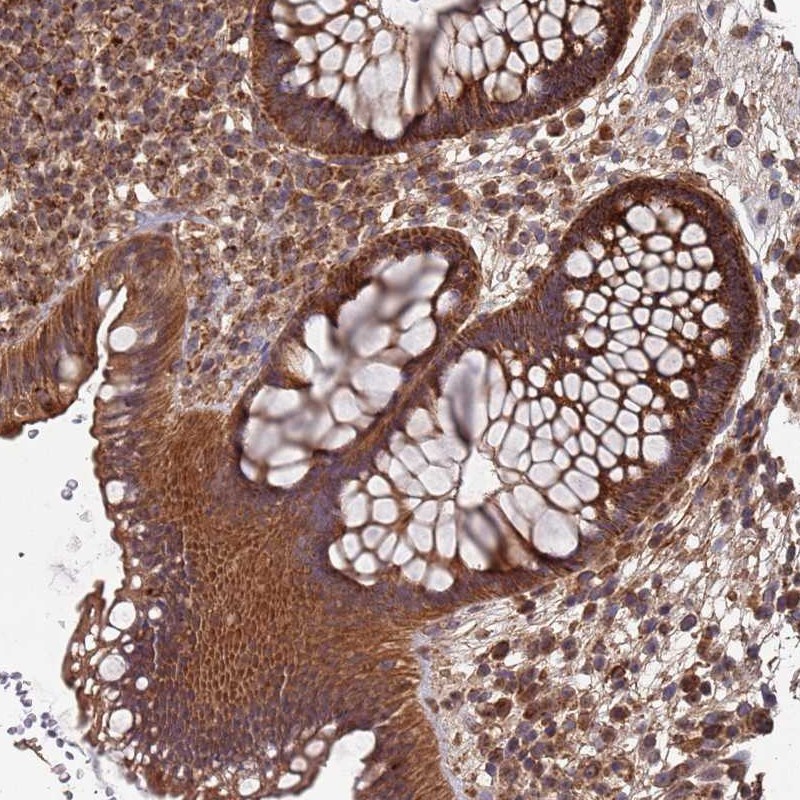

Immunohistochemical staining of human rectum shows strong cytoplasmic positivity in glandular cells.